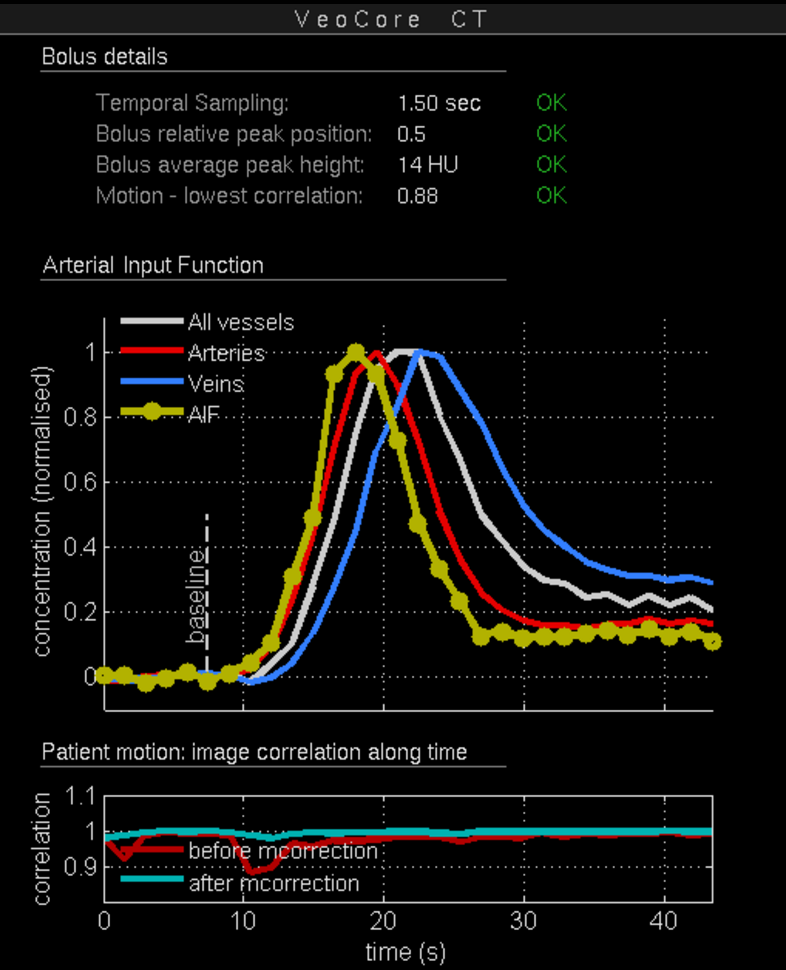

16.1. Overview

VEOcore is a fully automated image processing tool to calculate quantitative measures of affected brain tissue and healthy tissue. Therefore, this manual covers the instructions on how to interpret the results. It’s an extension the mRay Server application and the results can be viewed inside the mRay Client. Furthermore processed results can be automatically forwarded to the PACS.

16.2. Triggering the data processing

VEOcore does not have a user-interface. Data is processed fully automated on reception of DICOM series. All series should be sent in one rush, otherwise the data processing might be invoked multiple times, and result images might appear in the target PACS multiple times.

For MR and CT, the following DICOM images can be sent to the application. For details on series naming conventions as well as compatible and recommended measurement parameters such as slice thickness, repetition times etc. please refer to the Annex.

16.2.1. Computed Tomography (CT))

-

CT perfusion (VPCT)

Repeatedly acquired volumes of low-dose CTs acquired during injection of a contrast bolus. This series is often called VPCT (Volume-Perfusion-CT). -

Non-contrast native CT image (optional)

Native image before contrast injection with a reconstruction kernel optimised for brain tissue. Sending this image is optional, but recommended. If sent together with the VPCT, it is used as background for the overlay with the segmented core and mismatch volume.

16.2.2. Magnetic Resonance Imaging (MRI)

-

MR perfusion (DSC-Perfusion) (optional)

Repeatedly acquired volumes of echo-planar imaging acquired during injection of a contrast bolus. This measurement technique is often referred to as DSC-Perfusion (Dynamic-susceptibility-contrast perfusion). Sending a perfusion measurement is optional in MR. If not send, only the infarction core will be segmented based on the ADC (see below). -

MR ADC

Apparent-Diffusion-Coefficient (ADC), berechnet aus einer diffusions-gewichteten Sequenz (DWI-MR). Das senden des direkt am MR-Scanner berechneten ADC ist unbedingt notwendigan ADC, VEOcore berechent keinen ADC selbst aus den DWI-Daten. -

MR DWI (optional)